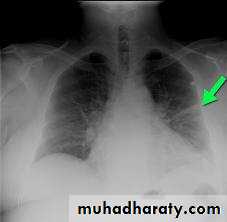

CXR may show opacities (of any size or shape); more specifically it may show horizontal linear opacities or wedge shaped pleural based opacities. Pleural effusion or raised hemidiaphragm may be noticed.

CXR is commonly normal (or show subtle oligaemia).